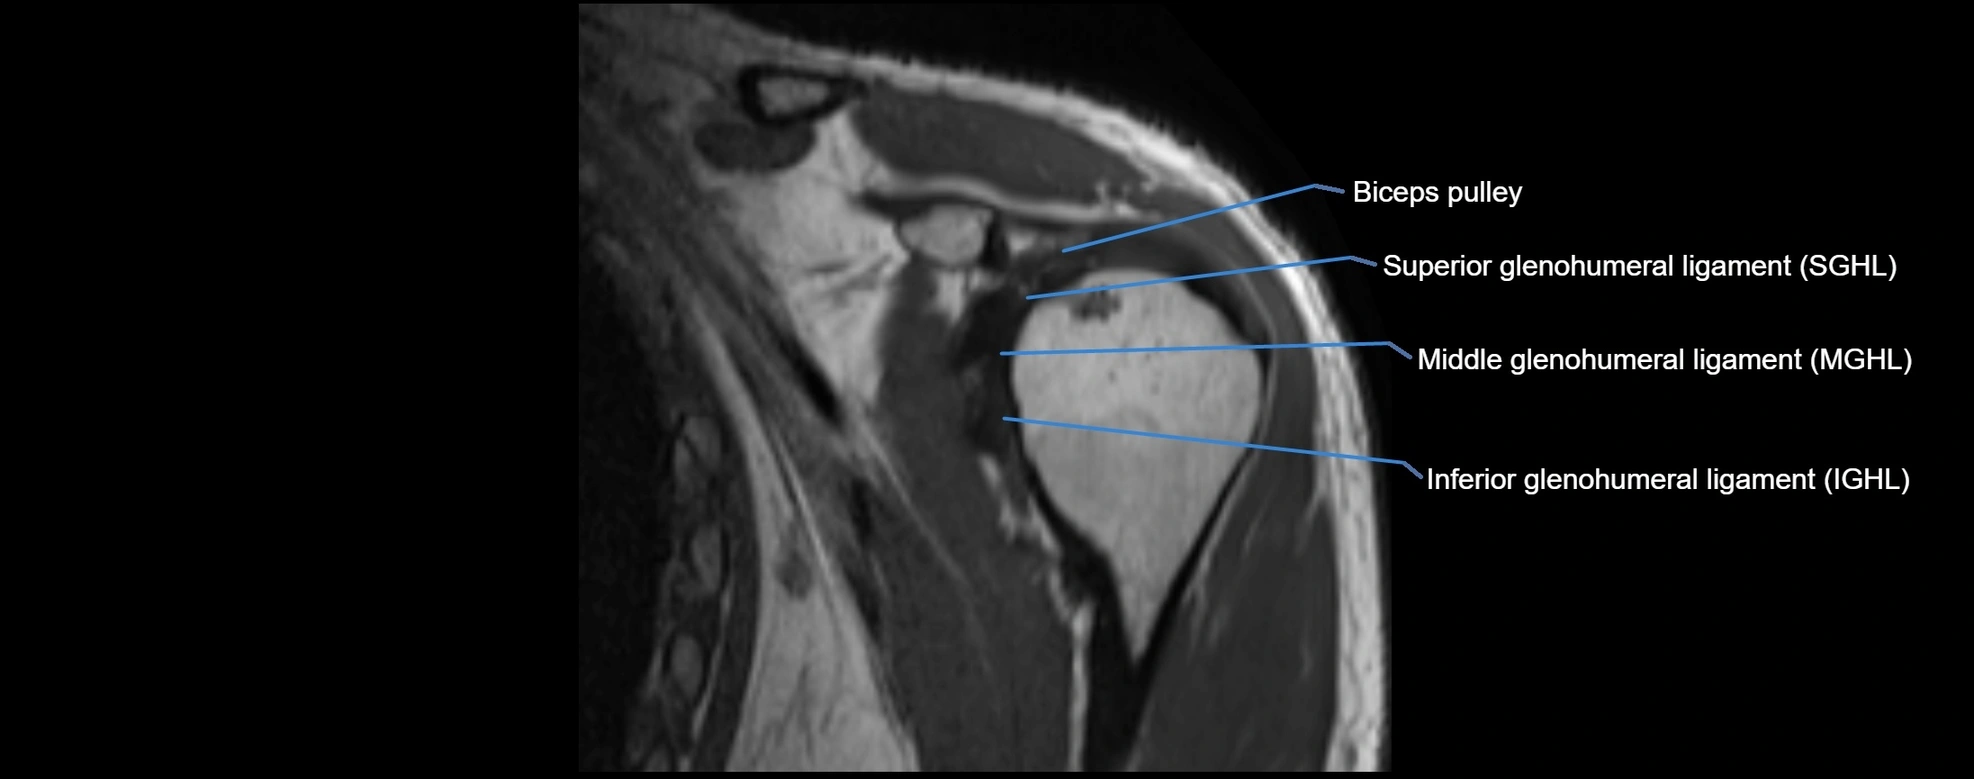

MRI Appearance

• T1-weighted images:

• Normal ligament: Low signal (dark linear band) spanning acromion to clavicle.

• Surrounding fat planes: Bright, delineating the ligament clearly.

• Marrow of clavicle and acromion: Bright due to fatty content.

• Tears: Discontinuity or irregular thickening with intermediate-to-bright signal.

• Chronic injury: Thinning, fraying, or irregular low-signal fibers with adjacent scarring.

• T2-weighted images:

• Normal ligament: Low signal, homogeneous.

• Partial tear or sprain: Focal hyperintensity or thickening.

• Complete tear: Discontinuity with fluid-bright gap between clavicle and acromion.

• Associated edema: Bright signal in distal clavicle or acromion marrow.

• Proton Density Fat-Saturated (PD FS):

• Normal ligament: Low signal, uniform thickness.

• Partial tear or sprain: Bright signal or contour irregularity.

• Complete tear: Clear discontinuity with bright signal gap and joint effusion.

• Excellent for assessing joint capsule, coracoclavicular ligaments, and periarticular edema.

MRI images

image